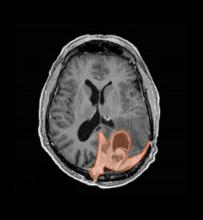

Stem cells are the body’s building block cells that can develop into other cells, such as blood cells. A stem cell transplant — a procedure that replaces unhealthy stem cells with healthy ones — helps increase children’s chances of surviving blood cancers, like leukemia, and other blood-based illnesses.

Before a transplant, patients receive chemotherapy and radiation to ‘condition’ their body to accept the new, healthy stem cells. The conditioning eliminates the body’s current stem cells, weakens the immune system, and destroys any remaining cancerous cells. Even so, Chris knew the long-term prognoses for these kids were grim. Historically, only a third of blood cancer patients who received a stem cell transplant survived three years without relapse.